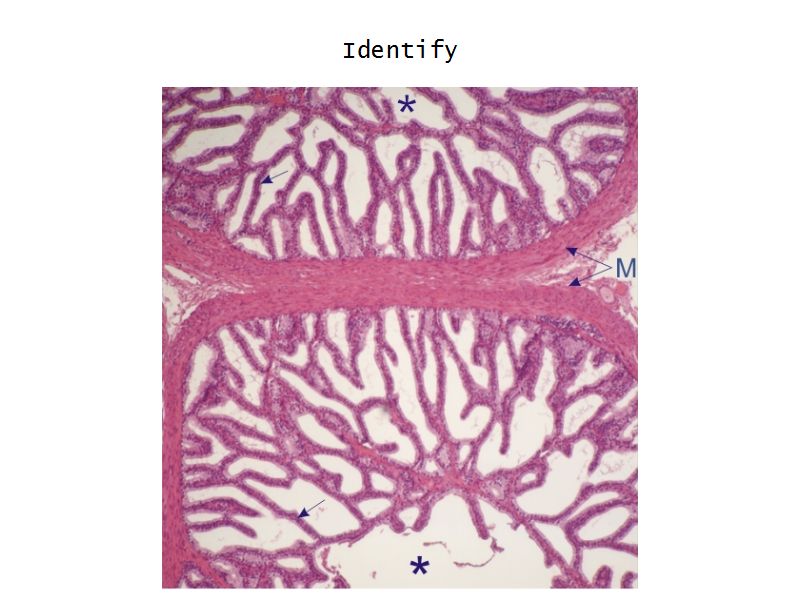

Vesicula seminalis

Slide 81Vesicula seminalis

- Mucosa

- Epithelium

- Lamina propria

- Muscle layer

Mucosa

- Lumen

- Irregular

- Store secretions

- Pseudostratified columnar epithelium

- Lamina propria

- Contains AVL

- Folded mucosa ^^ surface area

Muscle layer

- Inner circular

- Outer longitudinal